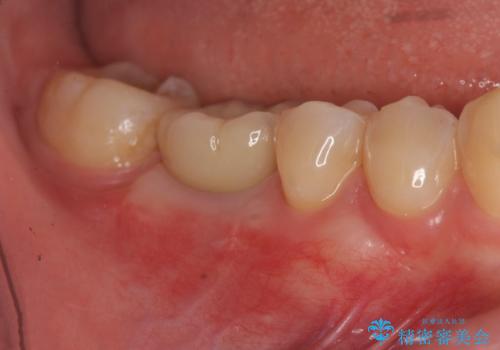

[ 歯肉縁下カリエス ] 歯周外科を行い、歯を残す

![[ 歯肉縁下カリエス ] 歯周外科を行い、歯を残すの症例 治療前](https://seimitsushinbi.jp/wp/wp-content/uploads/2023/01/9c47fe75d13e5b920ea2ccdb0dc8ed3b-500x350.jpg?v=1673602326)

![[ 歯肉縁下カリエス ] 歯周外科を行い、歯を残すの症例 治療後](https://seimitsushinbi.jp/wp/wp-content/uploads/2023/01/fc11ac5ecfd3722f9c91e063fe42c4f3-500x350.jpg?v=1673602360)